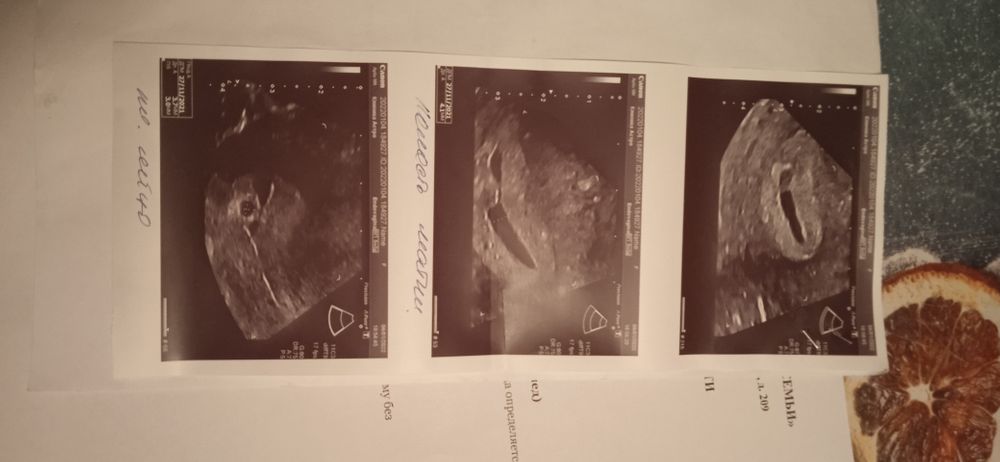

Назначили ДЮФАСТОН, МАГНЕЛИС Б6 И ТРАКСИПАМ. СКАЖИТЕ ПОЖАЛУЙСТА, НОРМАЛИ ЛИ ЧТО ЖМ НЕ ОПРЕДЕЛЯЕТЬСЯ И ЭМБРИОН?

Желтое тело есть, плодное яйцо есть, диаметр плодного яйца хороший, а гематому будут наблюдать, все соответствует сейчас.

Трижды мама, там же в заключении написано что ЖМ не определился, или я походу совсем уже с ума сошла и не чего не понимаю

Анастасия Величкина, ЖМ И жел тело это не одно и тоже. У вас все по сроку, растите🙏

Беременность 6-7 недель, что соответсвует вашему сроку по месячным, но возможно есть гематома. За ней надо в динамике следить и обязательно с врачом обсудить это.

Переживаю что ребёночка не видно, и так же не понимаю откуда эта гематома могла появиться